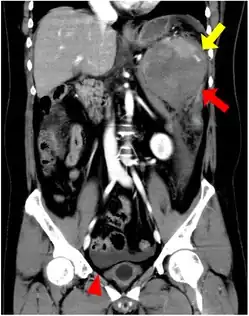

Gross pathology of an accessory spleen -

Ultrasonography of an accessory spleen.

If splenectomy is performed for conditions in which blood cells are sequestered in the spleen, failure to remove accessory spleens may result in the failure of the condition to resolve.[1] During medical imaging, accessory spleens may be confused for enlarged lymph nodes or neoplastic growth in the tail of the pancreas,[5] gastrointestinal tract, adrenal glands or gonads.[2]